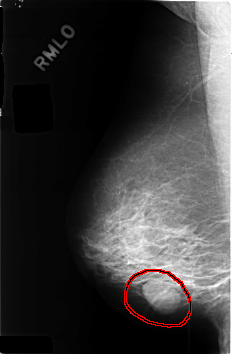

C_0404_1.RIGHT_MLO

RIGHT_MLO LINES 4592 PIXELS_PER_LINE 3008 BITS_PER_PIXEL 12 RESOLUTION 50 OVERLAY

FILE: C_0404_1.RIGHT_MLO.OVERLAY

TOTAL_ABNORMALITIES 1

ABNORMALITY 1

LESION_TYPE MASS SHAPE OVAL MARGINS CIRCUMSCRIBED

ASSESSMENT 3

SUBTLETY 5

PATHOLOGY BENIGN

TOTAL_OUTLINES 1

BOUNDARY